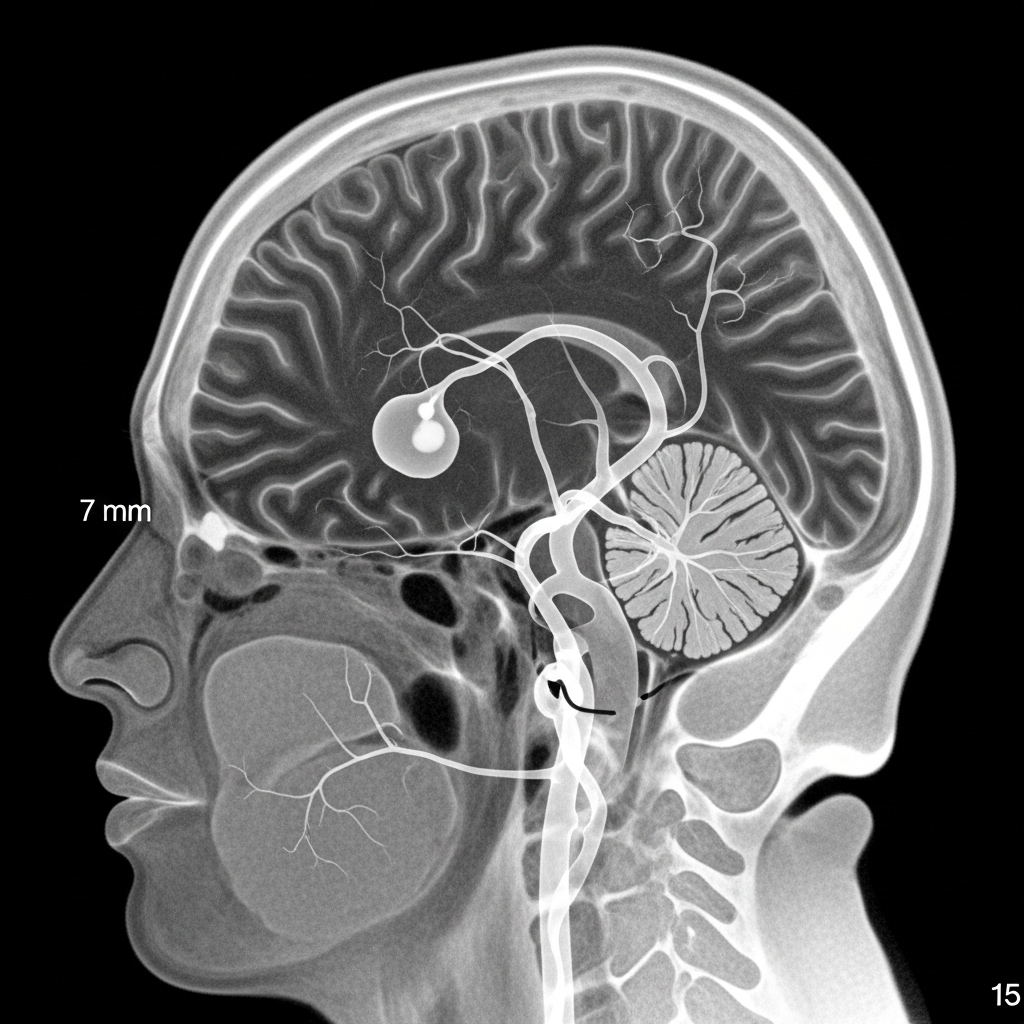

A cerebral aneurysm is a weak spot in a brain blood vessel that bulges like a small balloon. Most aneurysms are silent and cause no symptoms, but the danger arises if the aneurysm ruptures, causing bleeding in the brain. Symptoms of a rupture can include a sudden severe headache, nausea, vomiting, vision problems, or loss of consciousness, making it a medical emergency. Not all aneurysms burst; some remain small and harmless, while others grow over time. Diagnosis is usually made through brain imaging, often performed for other reasons. Treatment depends on the aneurysm’s size and location and may include regular monitoring or interventions to prevent rupture. Endovascular coiling is a minimally invasive procedure that fills the aneurysm with coils to block blood flow, while flow diversion devices redirect blood away from complex aneurysms to promote healing. In emergencies, coiling or surgical clipping is performed alongside intensive care to prevent re-bleeding and support recovery. Early detection and proper care are essential.